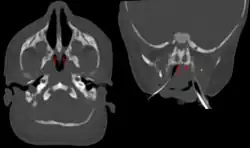

Bilateral membranous choanal atresia in CT scan

Choanal atresia is a congenital disorder where the back of the nasal passage (choana) is blocked, usually by abnormal bony or soft tissue (membranous) due to failed hole development of the nasal fossae during prenatal development. It causes persistent rhinorrhea, and with bilateral choanal atresia, an obstructed airway that can cause cyanosis and hypoxia.

Choanal atresia causes closure of the posterior choanae in the nasal cavity. Around 30% of these affect just the bone, while around 70% affect both bone and membranes. Bones affected can include the body of the sphenoid bone, the vomer, the medial pterygoid process of the sphenoid bone, and the horizontal plate of the palatine bone.[1]

Diagnosis is confirmed using CT scan.[1]This is also useful for differential diagnosis.[1]